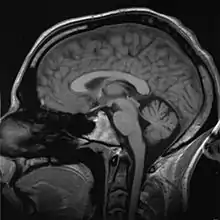

An MRI scan of a human head, an example of a biomedical engineering application of electrical engineering to diagnostic imaging. Click here to view an animated sequence of slices.

Imaging technologies are often essential to medical diagnosis, and are typically the most complex equipment found in a hospital including: fluoroscopy, magnetic resonance imaging (MRI), nuclear medicine, positron emission tomography (PET), PET-CT scans, projection radiography such as X-rays and CT scans, tomography, ultrasound, optical microscopy, and electron microscopy.